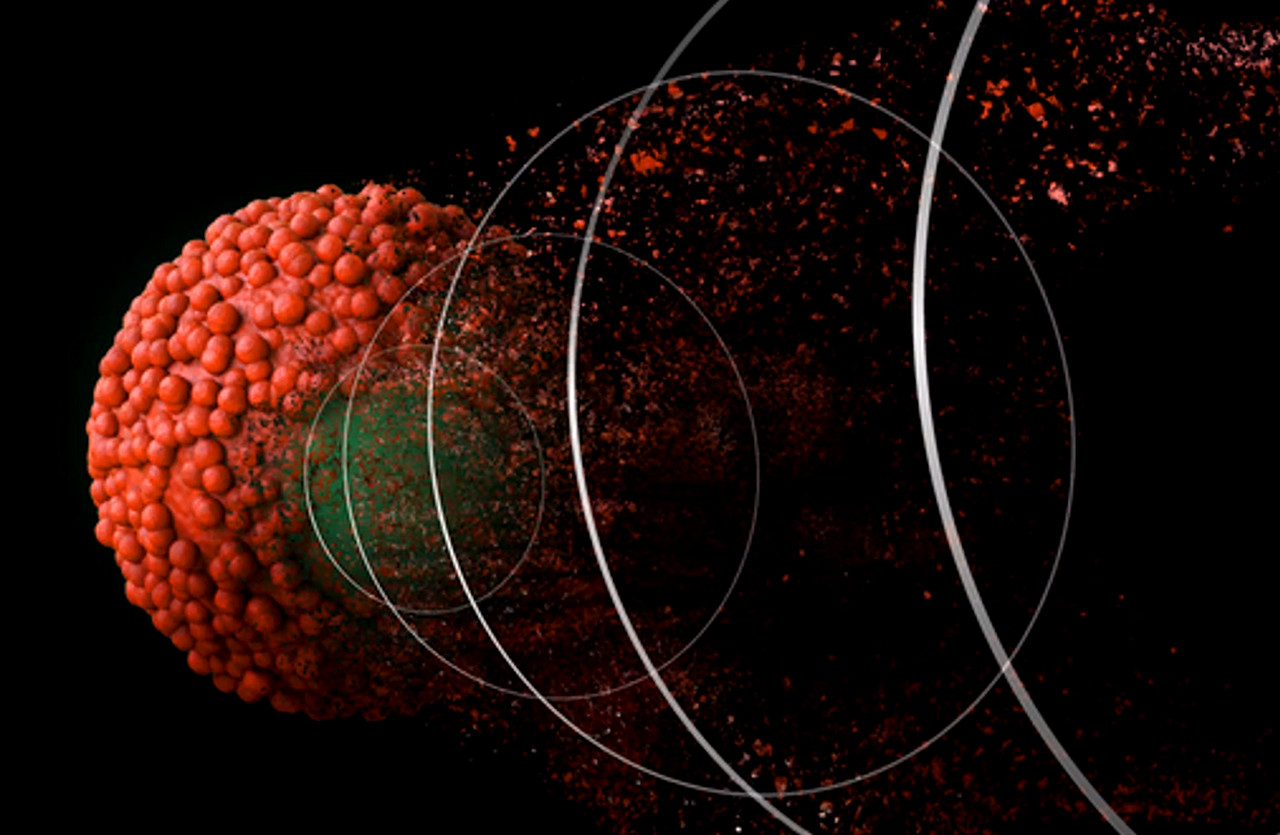

비가역적 전기천공술 (IRE)

비가역적 전기천공술 (IRE)는 종양에 전기 펄스를 주어 암세포를 죽이는 암치료법으로, 종양 부근에 있는 정상 세포는 전혀 영향을 받지 않는 암치료법 입니다.

이 암치료법은 사람의 간암, 췌장암, 갑상선암 등 혈관과 신경이 밀집한 국소적인 종양에서 치료적인 효과와 안정성이 입증되었습니다.

비가역적 전기천공술(IRE)은 고주파열로 암세포를 태워버리는 고주파절제(RFA)보다 안전하며 효과적입니다.

시술에는 종양 개수에 따라 30분~2시간 정도 소요됩니다.

• IRE를 통해 기대할 수 있는 효과

1. 주변 정상 세포를 손상시키지 않고 암세포를 죽입니다.

2. 수술이 어려운 경우에 선택할 수 있는 암치료 방법입니다.

• IRE는 어떤 아이들에게 적용할 수 있을까요?

1. 간암에서 간엽절제술 이후 전이가 되었으나 재수술이 어려운 경우

2. 간, 췌장, 갑상선 등에서 작은 크기의 종양이 초기 발견된 경우 (3cm 이하)